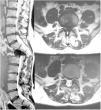

Cauda equina syndrome (CES) caused by lumbar disk extrusion is classically considered an indication of urgent surgery. CES can be subdivided into CESI (incomplete CES) and CESR (complete CES with urinary retention and incontinence). This paper evaluates the long-term functional outcome of a CES cohort operated on due to disk herniation.

ResultsTwenty-two patients were included (median age 44 years). Eight patients were CESR and 14 CESI. Median time from symptom onset to diagnosis was 78h (range, 12–720h), and from diagnosis to surgery 24h (range, 5–120h). Median follow up was 75 months (range, 20–195 months). At the end of follow up, in the CESR group (median time from diagnosis to surgery, 23h) only pain significantly improved after surgery (p=0.007). In the CESI group (median time from diagnosis to surgery 23h) low back pain, sciatica and urinary sphincter function significantly improved (p<0.001). There were no significant differences between early (<48h) operation (n=4) and late (n=18) in terms of sphincter recovery (Fisher's Exact Test, p=0.076).

ConclusionPain associated to CES improved both in the CESI and CESR groups. However, urinary sphincter impairment significantly improved only in the CESI group. No significant differences were found regarding long-term functional outcome between early and late surgery.